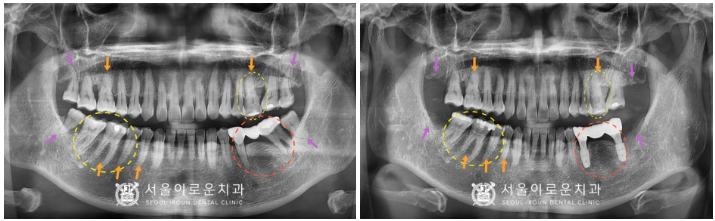

그리고 제일 불편감을 호소하셨던

왼쪽 아래 브릿지 보철물(#35,37)로

수복된 치아를 발치하고나서

주변 염증조직을 깨끗하게 제거한 뒤

뼈이식을 동반하여

임플란트 즉시 식립을 진행하였습니다.

발치 후 즉시 식립을 하게 되면

잇몸 조직의 손상과 출혈, 붓기도 적어

통증도 감소되며

치료 기간이 단축되는 장점이 있는데요.

임플란트 즉시 식립은

누구에게나 다 적용되는 것은 아니며,

구강 내 상황을 정밀하게 체크한 뒤

의료진의 판단하에

즉시 식립 여부를 결정하게 됩니다.

발치 후 즉시 임플란트를 진행하는 날

왼쪽 위아래 사랑니(#28,38)도

같이 발치를 진행하였으며,

왼쪽 잇몸이 어느 정도 아문 뒤

오른쪽 사랑니(#18,48)도

발치를 도와드렸고,

임플란트와 주변 치조골이

단단하게 결합되기를 기다리는 동안

다른 치료를 도와드렸는데요.

더불어 4개의 치아 (#26,45,46,47) 모두

치.아색과 동일한 인레이 재료로

수복을 도와드리면서

전보다 훨씬 더 심미적으로

구강환경이 바뀐 것을 확인할 수 있습니다.

임플란트 / 사랑니 발치

치경부 마모증 / 인레이

치료를 모두 마무리 한 모습입니다.